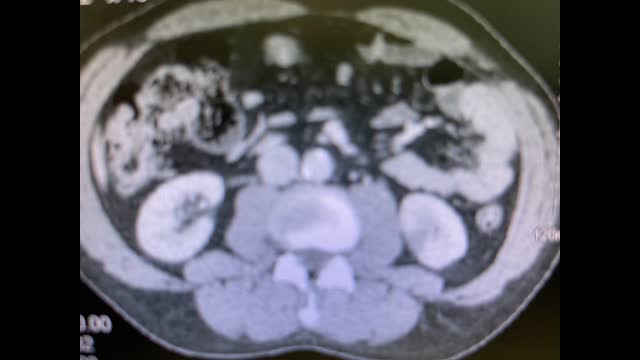

48-year-old man presents with acute onset right flank pain and nephrotic syndrome